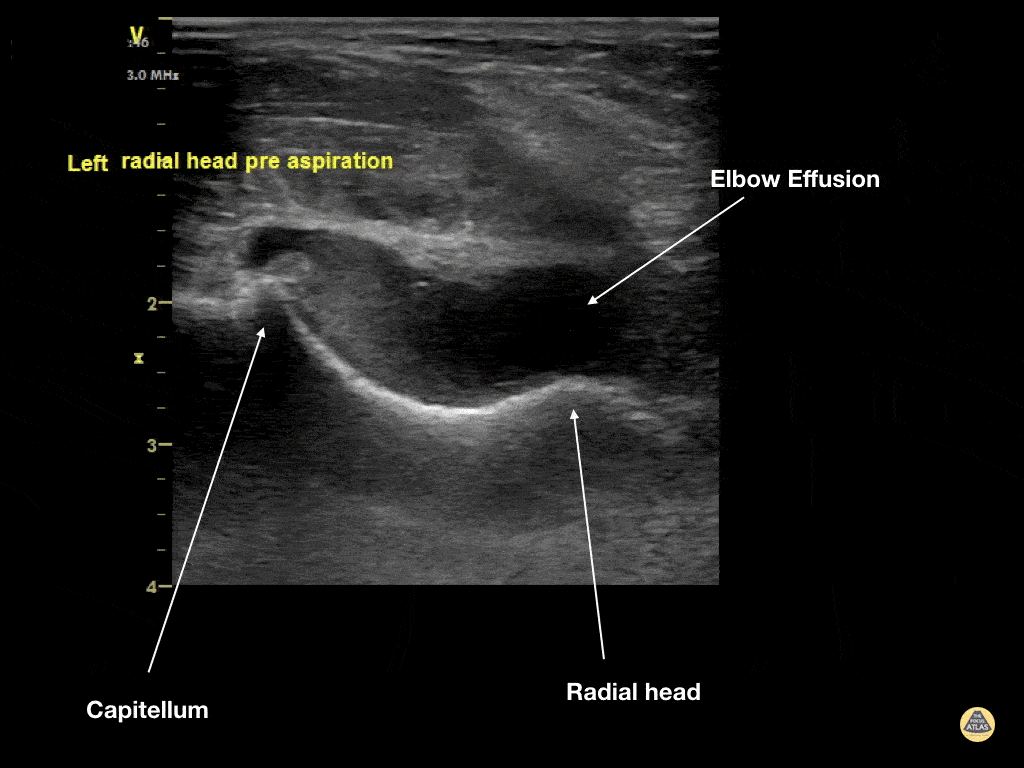

Musculoskeletal - Elbow Effusion (Traumatic)

Aspiration of traumatic elbow effusions may be considered in the management of radial head fracture. Slide a linear transducer along the forearm towards the elbow until the radial head, effusion and capitellum are seen. Using an out of plane approach, insert a needle into the effusion. The syringe will fill itself under intrinsic pressure. Relief is often instantaneous and prolonged and the range of motion of the elbow will increase dramatically Dr Cian McDermott, Emergency Physician, Mater University Hospital, Dublin, Ireland